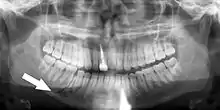

Panoramic radiographs have the capability to demonstrate a portion of the neck and display atheromas (calcifications in the carotid artery) which are an indication of both local and generalized (systemic) atherosclerosis. Atherosclerosis of the coronary arteries leading to myocardial infarction (heart attack), and atherosclerosis of the carotid artery leading to stroke are the number one and number three most common causes of death in the United States.[6]

There is interest to look at panoramic radiographs as a screening tool, however further data is needed with regards if it is able to make a meaningful difference in outcomes.[7]

Epidemiology: general public and high risk groups

Additional research projects have further determined the prevalence rate of these atheromas in the general population (3–5%)[8][9] and among high-risk groups (over 25% in: recent stroke victims,[10] individuals with obstructive sleep apnea syndrome,[11][12][13] postmenopausal women,[14] type 2 diabetics,[15][13][16] individuals with dilated cardiomyopathy,[17][13] and among individuals who have received radiotherapy directed at the neck,[18][19]). These findings have been corroborated by other several other researchers.[20][21][22][23][13]

Atherosclerosis is attributed to risk factors that include cigarette smoking, hyperlipidemia, obesity, diabetes mellitus, and hypertension (high blood pressure). These factors, however, do not fully account for the risk of disease. Atherosclerosis has been conceptualized as a chronic inflammatory response to endothelial cell injury[24] and dysfunction possibly arising from chronic dental infection. In 2010, using the previously validated Mattila panoramic radiographic index to quantify the totality of dental infection (i.e., periapical and furcal lesions, pericoronitis sites, carious tooth roots, teeth with pulpal caries, and vertical bony defects), Friedlander’s group determined that individuals with carotid artery atheromas on their panoramic radiographs had significantly greater amounts of dental infection/inflammation than atherogenic risk-matched controls devoid of radiographic atheromas.[25][26] While the Mattila index had been previously used to relate the extent of dental infection to coronary artery disease, this research is the first to link the full range of dental disease that it measures to panoramic radiographs evidencing calcified carotid artery atherosclerosis.